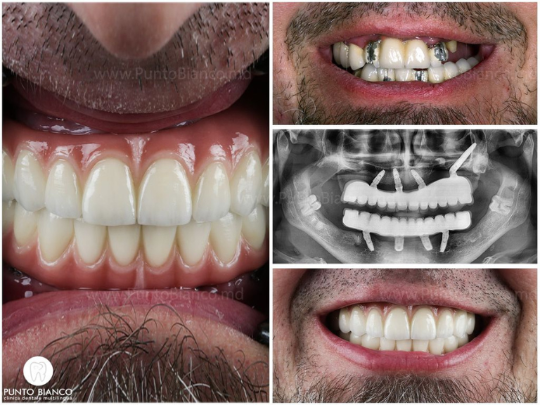

«Мы — одна из немногих стоматологических клиник Молдовы, которая не только обещает, но и действительно выполняет установку имплантов и фиксирует временные зубы уже в день операции или на следующий день. Это стало возможным благодаря современным технологиям, которыми оснащена клиника Punto Bianco (цифровые оттиски, выполненные с помощью самого современного интраорального сканера, 3D-томография прямо в клинике, собственная цифровая лаборатория), а также мультидисциплинарной команде с большим опытом в полном и сложном восстановлении зубных рядов.»